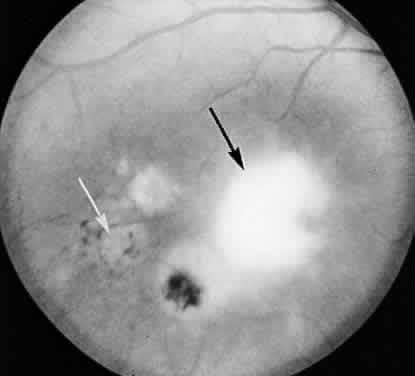

Researchers have had the opportunity to study the histopathologic characteristics of ocular toxoplasmosis in patients with AIDS and other immunosuppressant conditions at autopsy because disseminated toxoplasmosis is often a fatal disease (Fig. 5).61,77,106 Unlike disease in immunocompetent patients, parasites can occasionally be seen in the uveal tissue and there is scant cellular infiltration within retinal tissue. As with immunocompetent patients, however, the predominant site of infection appears to be the inner retina. The density of parasites is frequently greatest near blood vessels, suggesting newly disseminated disease rather than recurrence from tissue cysts within the retina.

Fig. 5. Light micrograph of a necrotic retinal lesion examined at the autopsy of a patient with AIDS and ocular toxoplasmosis. Tissue cysts (black arrow) and trophozoites (white arrows) are seen. There is little inflammatory material (hematoxylin and eosin). (Holland GN, Engstrom RE, Glasgow BJ et al: Ocular toxoplasmosis in patients with acquired immunodeficiency syndrome. Am J Ophthalmol 106:653, 1988. Copyright The Ophthalmic Publishing Company.)